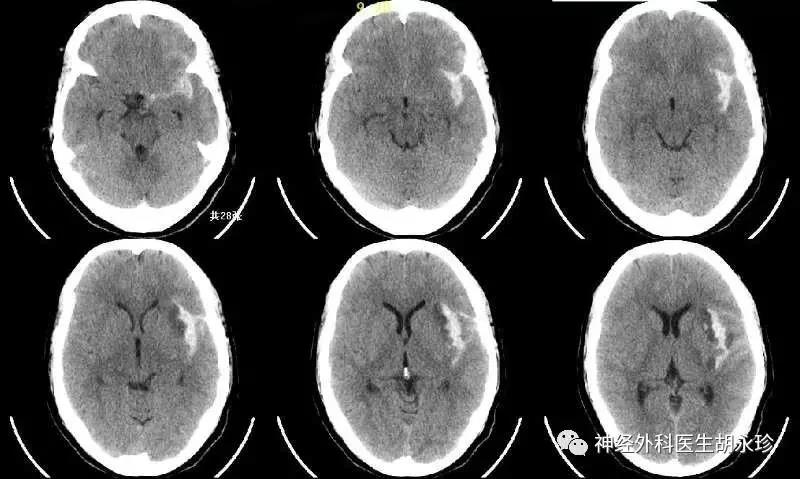

夏某,中年女性,因突發(fā)劇烈頭痛伴頭暈急診被送往外地某市級醫(yī)院救治,診斷“自發(fā)性蛛網(wǎng)膜下腔出血,左側(cè)顳葉腦內(nèi)血腫”,經(jīng)病情評估后考慮出血原因為“顱內(nèi)動脈瘤”,需要急診行手術(shù)治療。

但是,作為神經(jīng)外科醫(yī)生的我知道,顱內(nèi)動脈瘤性蛛網(wǎng)膜下腔出血是腦底部血管破裂,血液直接流入蛛網(wǎng)膜下腔引起的一種臨床綜合征,占急性腦卒中的 10% 左右。

顱內(nèi)動脈瘤破裂后的致殘率和致死率極高,有大約15%的患者來不及就醫(yī)直接猝死,首次出血的病死率為30%~35%,再次出血的病死率更高達(dá)60%~80%,幸存者亦多有殘疾。所以說轉(zhuǎn)院風(fēng)險還是很高的,況且患者目前在外市區(qū),轉(zhuǎn)往我院救護車行駛需要2-3小時車程。

最后患者安全轉(zhuǎn)往惠州三院,經(jīng)進(jìn)一步的評估,術(shù)前完善的檢查,了解患者無明顯手術(shù)禁忌癥后,李雪松主任向患者家屬說明病情,介紹手術(shù)方案,決定行開顱動脈瘤夾閉術(shù)。

手術(shù)過程十分順利,術(shù)中將動脈瘤安全夾閉,并將血腫予以清除,術(shù)后恢復(fù)良好,復(fù)查血管造影檢查可見動脈瘤夾閉完全,無腦梗死發(fā)生,患者及家屬很是高興。